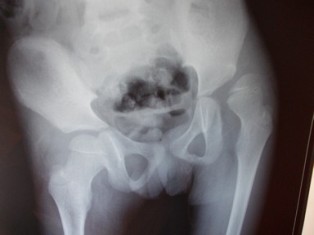

Best Scissoring Treatment In Pune

Radiograph of hip after surgery showing well reduced hip joint